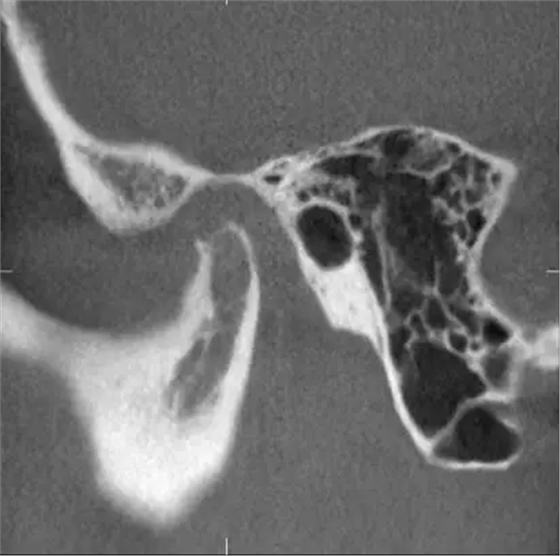

完全埋在牙槽骨里的下頜智齒,它本身倒是不出問(wèn)題。但是這些近中或水平阻生的智齒,會(huì)推擠下頜第二磨牙,導(dǎo)致第二磨牙伸長(zhǎng):

然后,第二磨牙造成咬合干擾、早接觸,前牙開(kāi) 牙合…………

甚至髁突吸收:

所以,這種智齒也還是要拔掉。